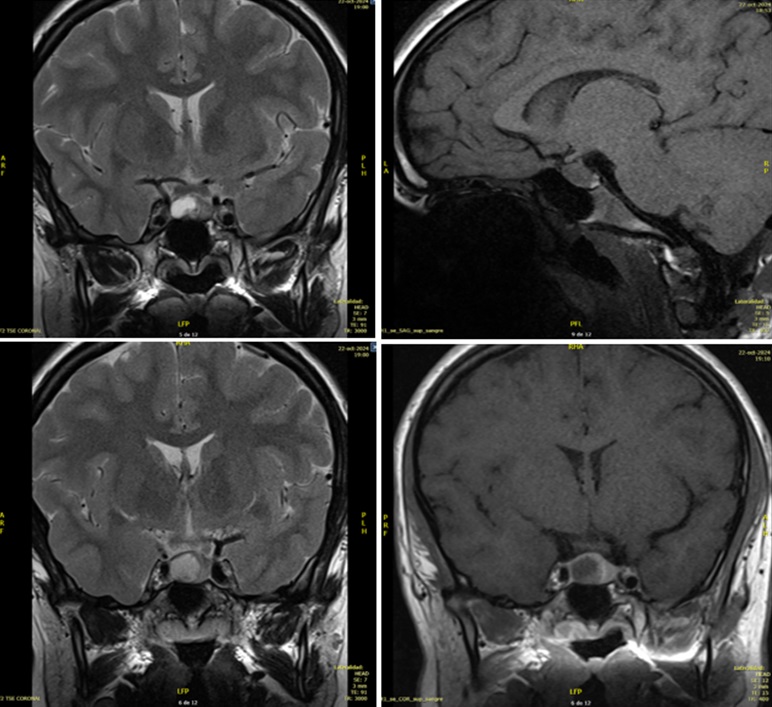

Ante dichos hallazgos se solicita una analítica de sangre con perfil hormonal, presentando hiperprolactinemia de 59,1 ng/ml sin otras alteraciones. Se deriva a Endocrinología, donde se repite la analítica de sangre en reposo, detectando valores más elevados en dos determinaciones (75,3 ng/ml y 86,8 ng/ml), por lo que se realiza resonancia magnética (RMN) cerebral, en la que se visualiza un macroadenoma hipofisario de 12 x 12 x 8 mm con área de degeneración quística que expande silla turca y contacta con el seno cavernoso derecho sin invadirlo (Figura 1). Se pauta tratamiento con cabergolina oral, a dosis inicial de 0,25 mg semanal y mantenimiento posterior con 0,5 mg semanales, con buena tolerancia. En el momento actual la paciente se encuentra clínicamente asintomática, con cifras de prolactina 10,9 ng/ml, pendiente de nueva RMN de control y valoración por Oftalmología.

| Figura 1. Lesión redondeada en margen derecho de la adenohipófisis (isointensa T1, hiperintensa T2), hipocaptante con realce tardío |

Para confirmar el diagnóstico, en caso de síntomas compatibles con hiperprolactinemia, se determinarán los niveles sanguíneos de prolactina a primera hora de la mañana, al menos dos horas tras despertarse, teniendo en cuenta que una sola determinación superior a 20 ng/ml no es fiable para el diagnóstico de hiperprolactinemia en niños debido a la secreción pulsátil10. En caso de sospechar causa tumoral, la prueba de imagen recomendada para el diagnóstico de estas lesiones hipofisarias es la RMN, en la que suele observarse en T2 una hipófisis hiperintensa aumentada de tamaño que puede comprimir estructuras adyacentes3.